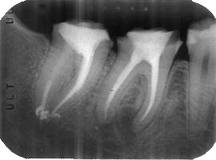

4- Grado de deterioro de la corona clínica por exposición

a caries o trauma

Grandes obturaciones cercanas a la cámara pulpar,

en la mayoría de las veces es directamente proporcional al

grado de calcificación de la cámara y de los conductos

radiculares. Ver primer imagen derecha

La falta de la corona clínica puede ser causa de

perforaciones accidentales. Ver segunda imagen derecha

La utilización sistemática de la radiografía periapical

pre-operatoria evitaría estos accidentes que suelen ser

comunes durante la práctica clínica.